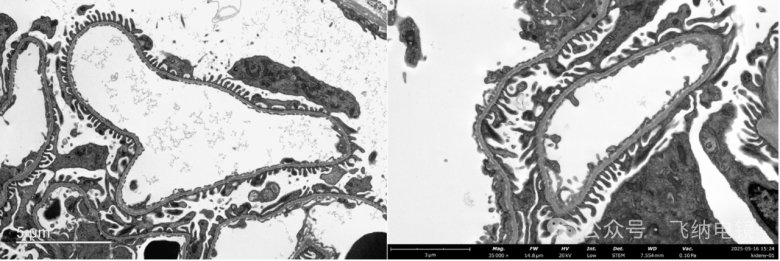

03组织切片——鼻粘膜上皮细胞

左:TEM;右:Pharos STEM